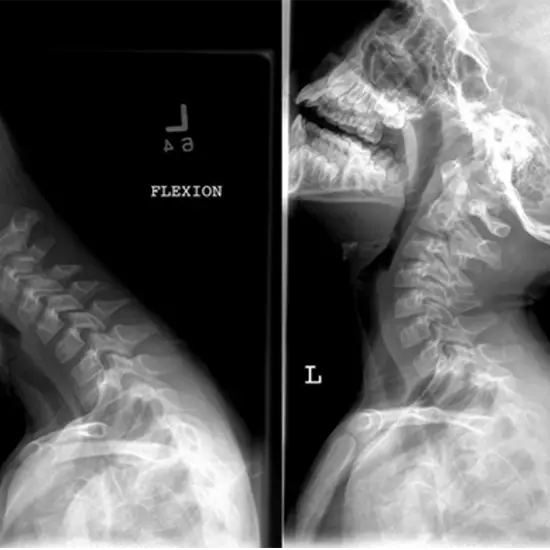

Cervical Spine Flexion and Extension on X-Ray View test to view the first seven cervical vertebrae (C1-C7) of the spinal column (backbone). It is also helpful in seeing the patient's intervertebral discs and the surrounding soft tissues, such as skin and muscles. Flexion/extension x-ray images identify ligamentous lesions undetectable by standard static views.

This test determines the source of persistent neck or upper back discomfort, identifies any suspected tumors or infections, and rules out any injuries or fractures to the spinal bones.